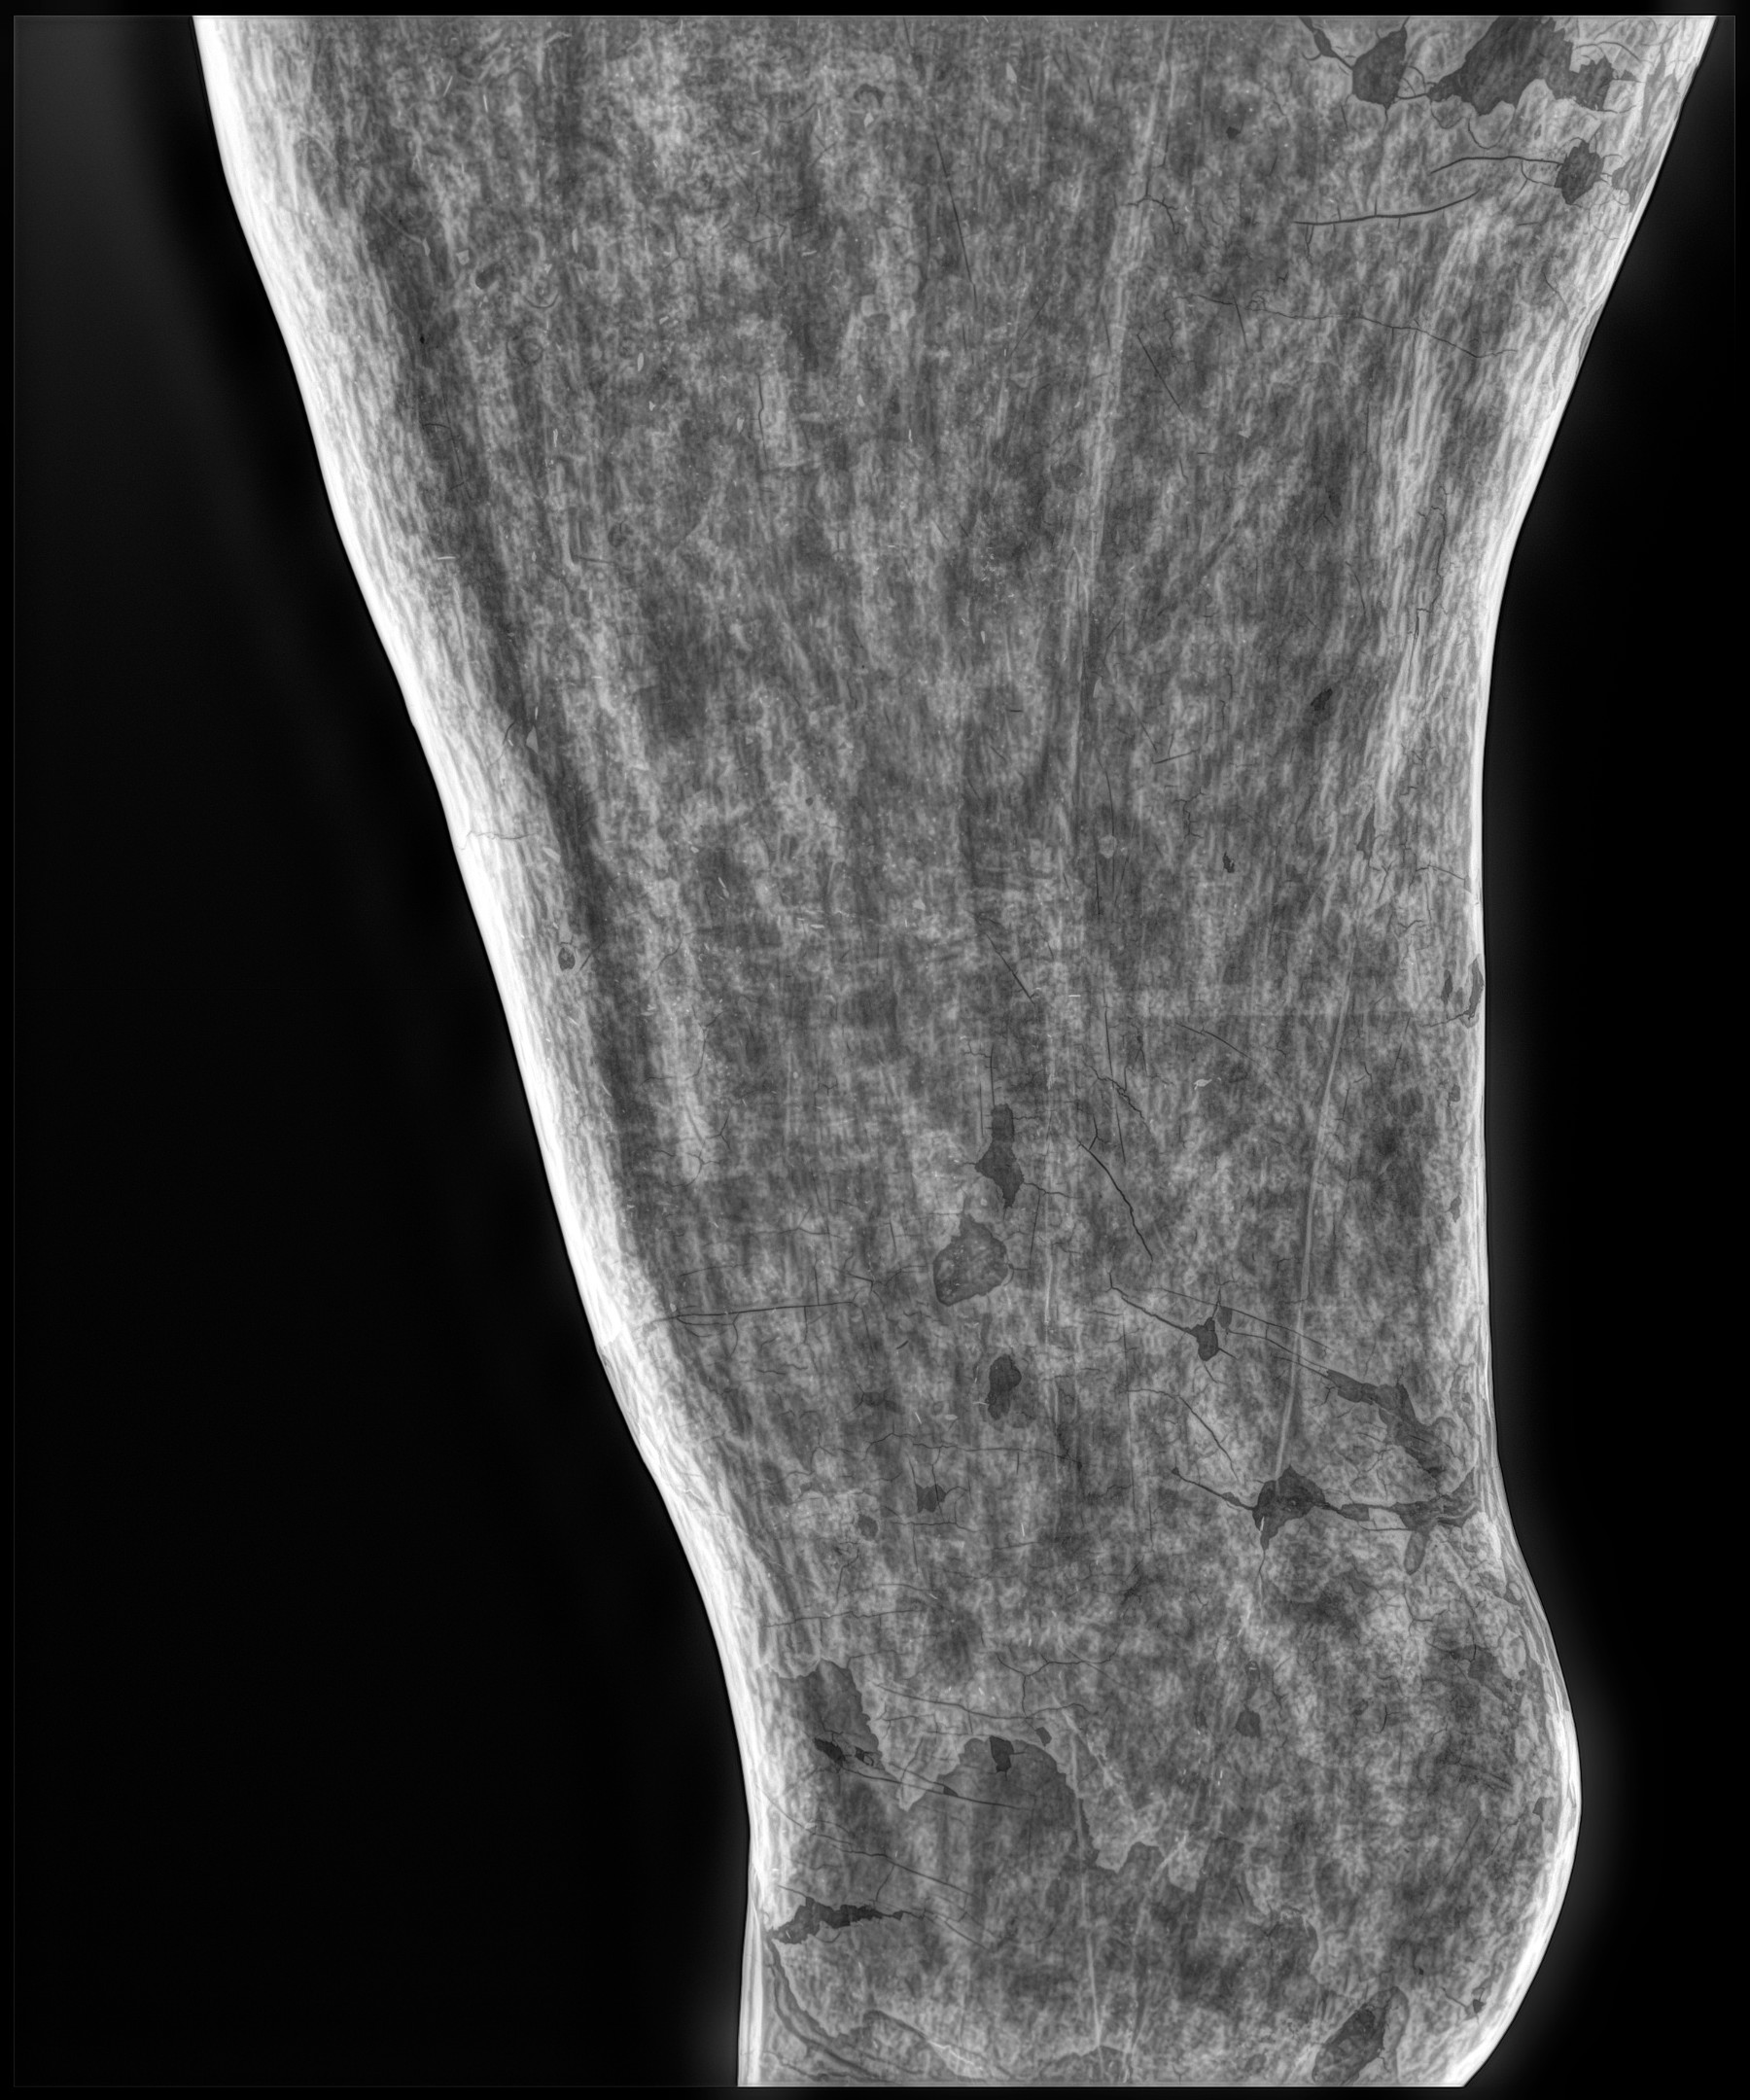

Cambios Térmicos en las Extremidades de Caballos,

Asociados a Golpes y su Evaluación por Termografía.

Los caballos de salto, en competencia, pueden derribar obstáculos y lastimarse. Si se golpean, no siempre claudican. Considerando al calor como un signo de inflamación, se evaluaron los cambios térmicos de 6 áreas de las extremidades torácicas y pelvianas de 23 caballos de salto en nivel de competencia de 1.05 a 1.60 m de altura, por medio de termografía durante 4 días de competencia (N=2208 áreas).